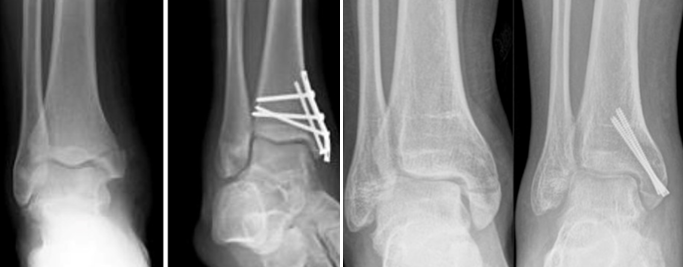

Gãy cả 2 mắt cá

Là gãy cả mắt cá trong lẫn mắt cá ngoài

Điều trị phẫu thuật

Bác sĩ sẽ mổ nắn xương và kết hợp xương cả mắt cá trong và mắt cá ngoài, khâu các dây chằng đứt lại để giữ vững cổ chân khi đi lại

Sau khoảng 12 tháng thì xương lành hoàn toàn và bác sĩ mổ tháo dụng cụ ra